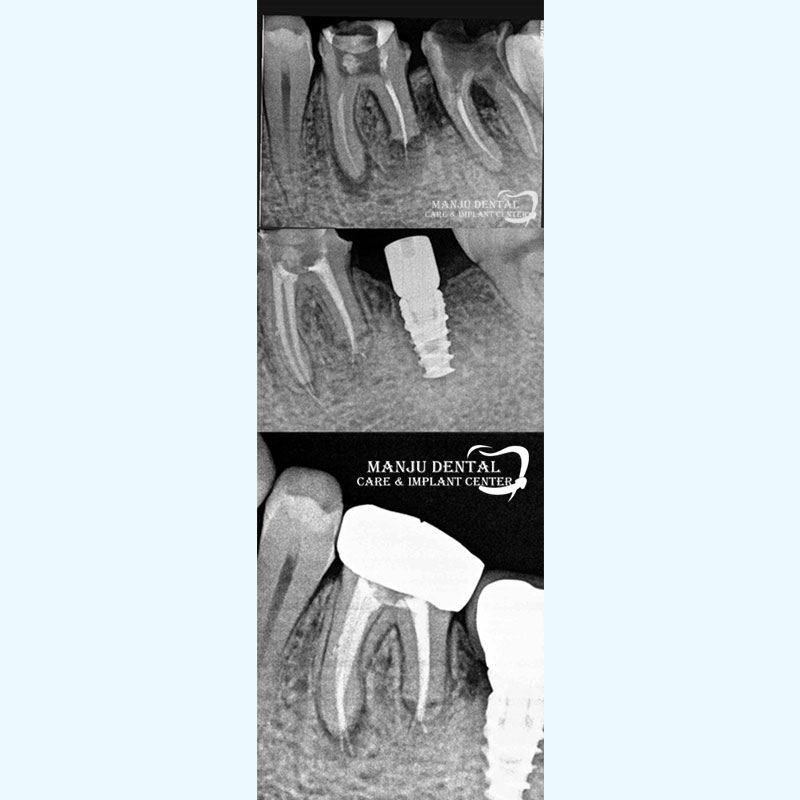

Full Spectrum Dental Care Extraction of Non Restorable Tooth, Implant Placement and Re-Rct of Adjacent Tooth